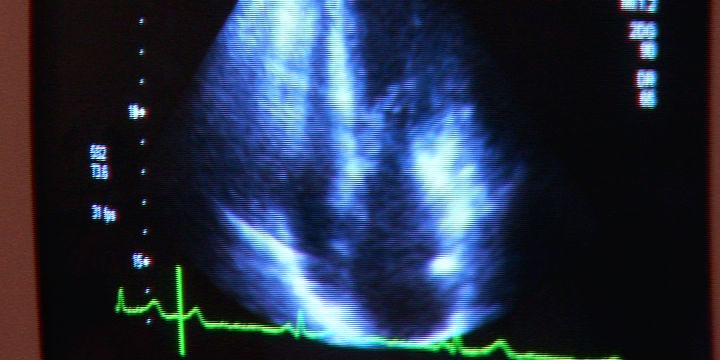

Die Herzinsuffizienz, auch bekannt als Herzschwäche, ist eine schwerwiegende Erkrankung. Um die Bevölkerung über die Risiken und aktuellen Möglichkeiten der Diagnostik, Therapie und Vorsorge aufzuklären, lädt das Universitätsherzzentrum Thüringen des Universitätsklinikums Jena am 8. November zu einem Herz-Seminar ein. Es ist kostenlos für Patienten und Angehörige und beginnt um 16.30 Uhr in der Uni-Aula am Fürstengraben. Herzexperten und niedergelassene Kollegen sprechen etwa über Fallbeispiele, Leben mit einem Defibrillator, Sport und Rehabilitation. Die Veranstaltung des Universitätsherzzentrums Thüringen, in Kooperation mit der Deutschen Herzstiftung ist Teil der bundesweiten Herzwochen. cd